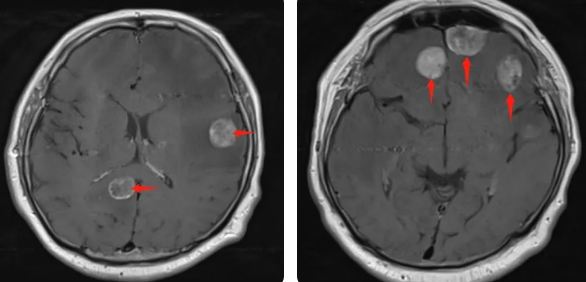

無獨有偶,60歲的左肺癌患者石先生,在外院接受了手術(shù)治療,結(jié)果術(shù)后10月出現(xiàn)腫瘤腦轉(zhuǎn)移,頭部增強MRI顯示:顱內(nèi)多發(fā)占位性病變伴水腫,接二連三的重擊讓石先生出現(xiàn)表情淡漠,沉默寡言,絕食等抑郁癥狀,VMAT放療技術(shù)與心理疏導雙管齊下,3周的治療后顱內(nèi)轉(zhuǎn)移病灶顯著縮小,部分甚至消失,困擾石先生的頭痛、頭暈癥狀也不復存在,石先生重拾對生活的希望,也對未來的治療充滿信心。